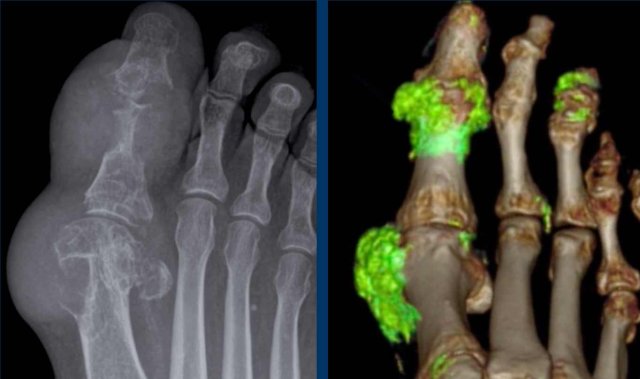

Continue with the Dual Energy CT...

Dual Energy CT in a patient with gout and urate crystal depositions Dual Energy CT in a patient with gout and urate crystal depositions

Dual Energy CT of the same patient with gout showing the urate crystal depositions.

In this 3D reconstruction the crystal depositions are color coded green and can be seen surrounding the MTP joints and at the insertion of the right achilles tendon (arrow).

The green pixels in the nail beds of digitus 1 and 5 on the left are artifacts caused by keratin in thickened nails.

Dual Energy CT is a noninvasive method of urate crystal detection that can make joint aspiration unnecessary.

Dual Energy CT simultaneously scans the subject at two different energy levels.

Because urate crystals show different attenuation at these energy levels, the crystals can easily be identified with high accuracy.

Another case with typical gout tophi and juxtaarticular erosions on plain films.

Dual Energy CT shows gout attenuation in MTP1, MTP2 and interphalangeal joints of the 3rd digit.

DECT is useful for the diagnosis when findings are not so typical.

It is also very useful to show the extent of disease.